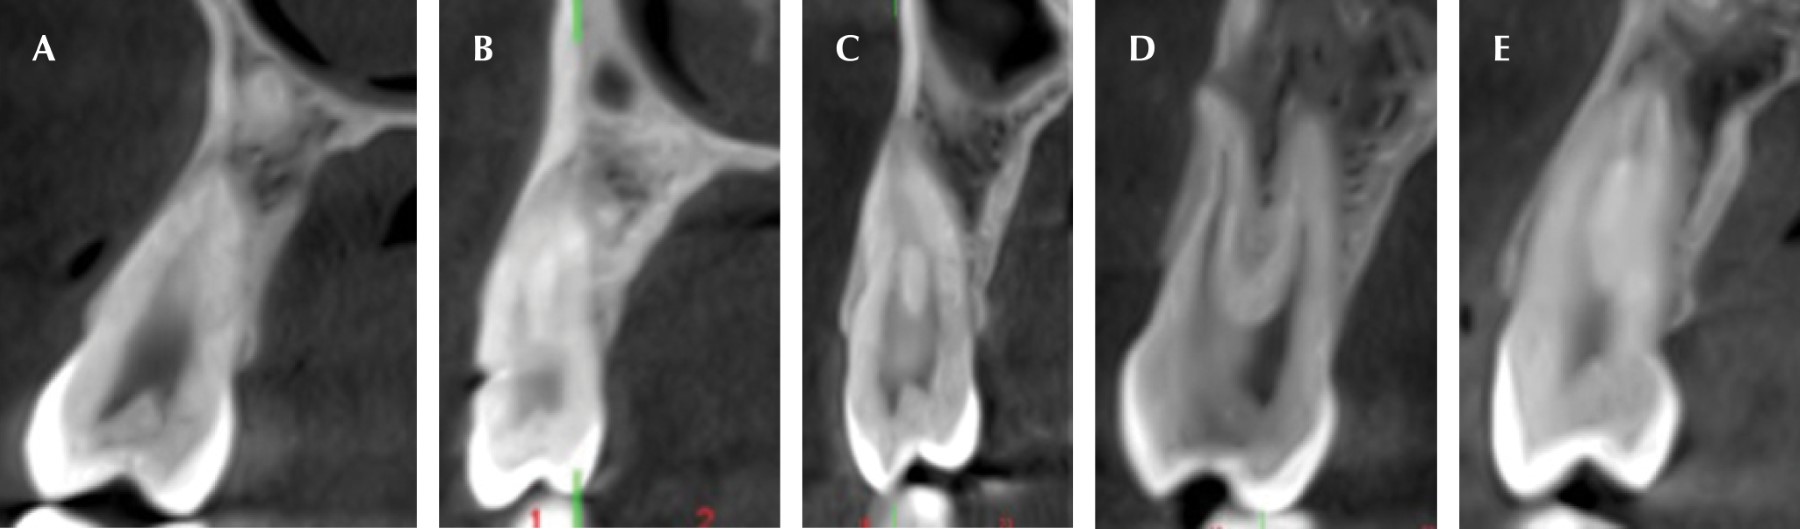

El objetivo de este trabajo es analizar la frecuencia del tipo de morfología interna de los conductos radiculares de los primeros premolares superiores, según la clasificación de Vertucci y el número de raíces mediante CBCT, en una población de 50 individuos (100 primeros premolares) de nacionalidad argentina, con una edad de entre 11 y 70 años; al comparar los datos obtenidos estadísticamente con la bibliografía actual. Se tendrá en cuenta la edad, el sexo y el lado derecho e izquierdo (Figura 2).

Figura 2